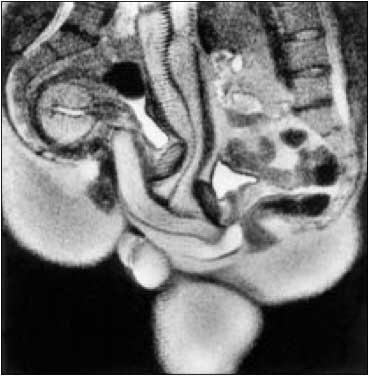

Medical Photos